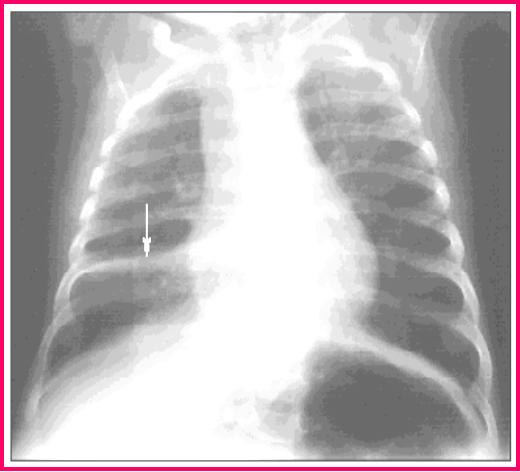

肺不张

3月龄女婴患肺炎后情况:

胸部 X 线检查所见:右下叶

肺不张的 锲形阴影(箭头)

节段性肺炎

(segment pneumonia)

5 岁男孩患节段性肺炎

胸部 X 线检查 :见左中

肺野羽毛 状阴影(箭头)